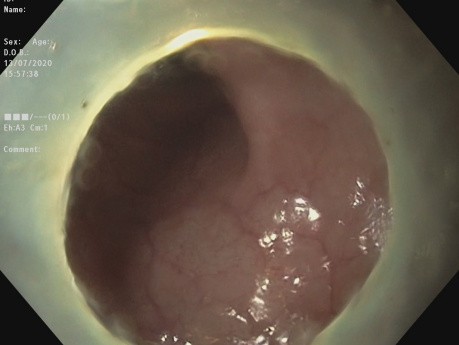

Płaska zmiana LST-G w odbytnicy

Wideo ukazuje pEMR zmiany w odbytnicy. Płaska zmiana LST-G (Polipowata zmiana typu LST-G (ang. laterally spreading tumor, granular)) w odbytnicy.